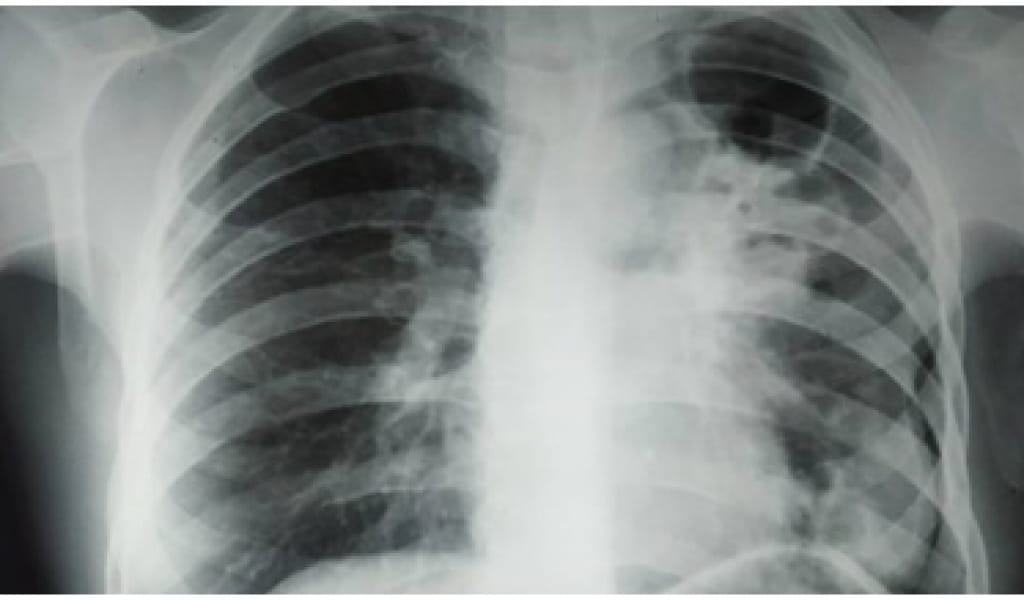

КОРОНАВИРУС ӨРШІДІ: БІР ТӘУЛІКТЕ АУРУХАНАҒА 151 АДАМ ЖАТҚЫЗЫЛДЫ

Наурыз мерекесі күндерінде енгізілген локдаунға қарамастан Алматы облысындағы эпидемиологиялық жағдай күрделене түскен. Коронавируспен ауырғандар саны екі есеге артып, бір тәулікте 104...

Соңғы аптада коронавируспен ауырғандардың өсу қарқыны Алматы облысында 0,6 процентті құрап, өткен тәулікте 99 жағдай тіркелген. Инфекциялық стационардың толымдылығы 43...